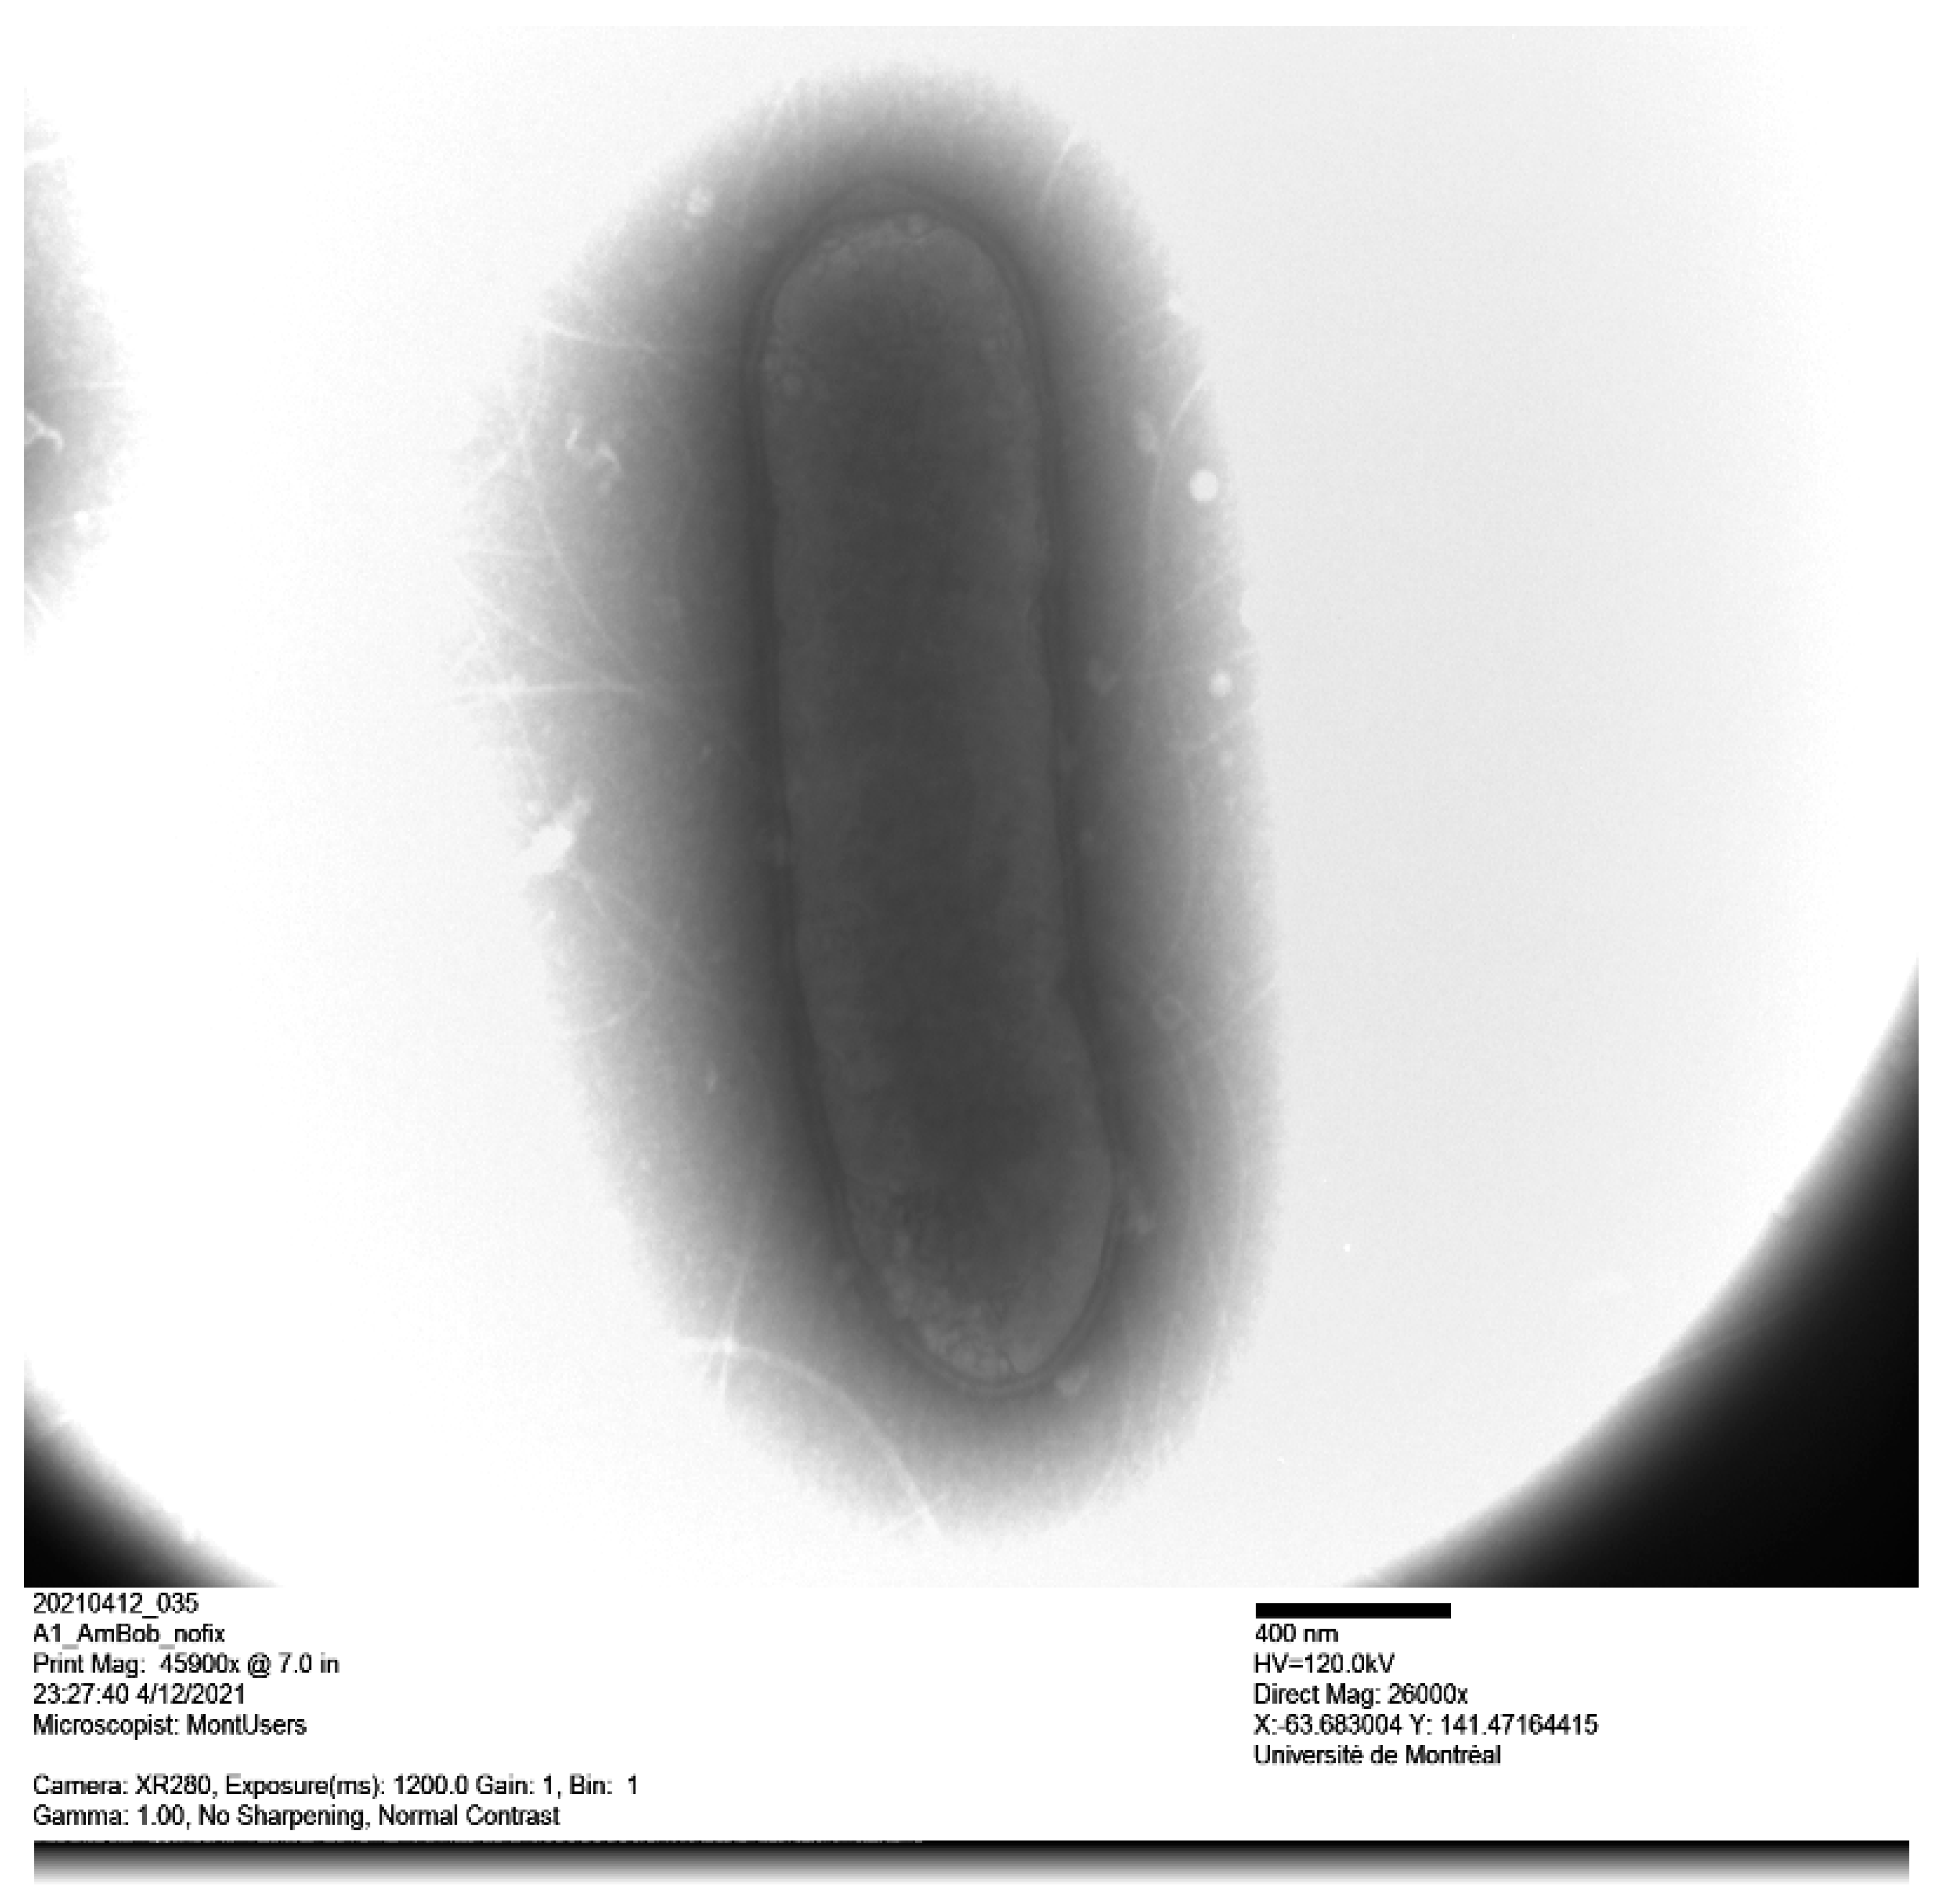

Cells of strain kh20T were non-motile, non-spore-forming, obligate anaerobes and Gram-negative rod-shaped. When inoculated on TSA, cells grew mostly singly and were 0.7 × 2.5 μm in size (Figure 2). After 48 h of growth on TSA, the colonies increased in size (0.2–0.3 mm in diameter) and were grey, circular, and convex. Strain kh20T was grown in an anaerobic atmosphere at pH 6 and 7.5, NaCl concentration less than 5 g/L, and temperatures between 28–37 °C. Strain kh20T exhibited positive catalase activity, and negative oxidase and urease activity. Nitrate was not reduced to nitrite. Bile was resistant. Using API® ZYM and Rapid 32A strips, positive enzyme reactions were obtained for alkaline phosphatase, galactosidase (α and β), β-glucosidase and N-acetyl-ß-glucosaminidase. In addition, esterase, esterase lipase, acid phosphatase and naphthol-AS-BI-phosphohydrolase were detected on API® ZYM. When tested with Rapid 32A strips, positive reactions were also obtained for glutamyl glutamic acid arylamidase, glutamic acid decarboxylase, proline arylamidase, leucyl glycine arylamidase, phenylalanine arylamidase, tyrosine arylamidase, alanine arylamidase, and glycine arylamidase. According to the API® 20A kit, strain kh20T hydrolyzed esculin and fermented D-glucose, D-lactase, glycerol, D-cellobiose, D-mannose, D-raffinose, and L-rhamnose. All other tests were negative (Table 1). Chemotypic analysis showed that strain kh20T was primarily composed of cellular fatty acids (Table 2) iso-C15:0 (26.60%), anteiso-C15:0 (19.90%), iso-C17:0 (17.20%), and anteiso-C17:0 (10.80%). Minor amounts of other fatty acids were also present, including C16:0 (8.50%), iso-C16:0 (4.42%), iso-C15:0 3OH (1.76%), C18:0 (1.42%) and C15:0w5c (1.30%). In addition, strain kh20 produced CO2, hydrogen and ethanol. Main phenotypic characteristics of strain kh20T and those of its closely related neighbors are shown in Table 1. We acknowledge the fact that the comparison of fatty acid profiles may not be easily done between studies due to differences in the composition of media, age of the culture, temperature, and the availability of oxygen.

Figure 2.

Transmission electron microscopy of Alistipes montrealensis strain kh20T using a Tecnai G20 transmission electron microscope.

Cells were subcultured and grown in Trypticase Soy Broth (TSB) at 37 °C without shaking overnight. Cells’ suspension was deposited on a glow-discharged formvar carbon film on 300 mesh copper grids (FCF300-CU, EMS). Cells were stained with 1% ammonium molybdate for 5 s. Then bacterial cells’ morphology was assessed by electronic microscope analysis using Tecnai G20 (FEI company, Hillsboro, OR, USA) and Gram-stain using a Gram-staining kit according to manufacturer’s instructions (ThermoFisher). Gram-stain and cell mobility were observed using photonic microscope Motic AE2000 (Motic Microscope, Vancouver, BC, Canada). Sporulation was determined by subjecting the bacterium to thermal shock at 80 °C for 20 min. Catalase and oxidase production was also detected (bioMérieux SA, Marcy l’Étoile, France). Enzymatic profile and biochemical properties of strain kh20T were assessed using the API® ZYM, API® 20A and Rapid ID 32A identification systems according to the manufacturer’s instructions (bioMérieux). Cellular fatty acid methyl ester profile was analysed using both gas chromatograph (Hewlett Packard) and Microbial Identification System (MIDI) software, version 6.0. End products were detected using a chromatograph as previously reported [9].